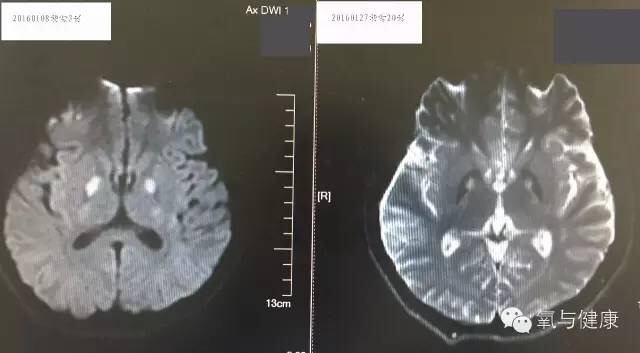

治疗经过:患者来院后完善检查,急诊予能量合剂、抗感染、保肝治疗及对症支持治疗,控制输液量及速度,防止心衰。积极对症治疗同时,2小时内急诊高压氧治疗。患者经过高压氧治疗后神志好转,但躁动明显,并出现双手震颤,结合头CT,考虑患者出现一氧化碳中毒脑病(无“假愈期”,影像表现为主要为底节区神经元损伤而非脱髓鞘改变,故考虑为一氧化碳中毒脑病而非迟发脑病),临时予以镇静,并予银杏叶制剂。高压氧治疗5次后,患者完全清醒,躁动消失,对答如常人,左手大鱼际水泡结痂,肝功、心激酶逐渐好转,仍有双手震颤,转回当地继续高压氧治疗。

转归:患者经过30余次高压氧治疗后我院复查,各项化验正常,症状恢复良好。